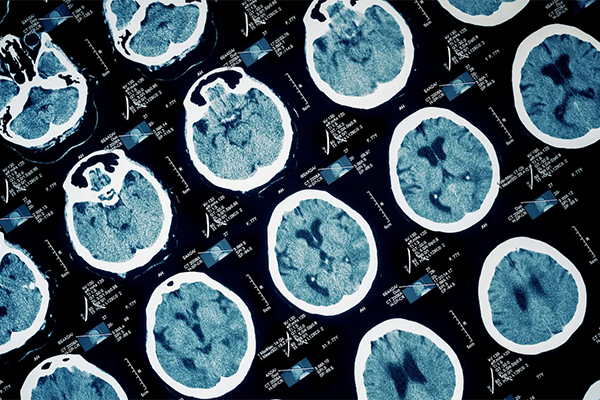

简介:基于Matlab从MRI图像中检测脑肿瘤(GUI界面) 编号:B10 大小:11M 环境:Matlab2018b 文档:付费文档撰写 配置:付费远程配置 运行:代码已经通过测试,可正常运行! 项目说明: 1.run brain_mri_tumour_detection.m 主题授权提示:请在后台主题设置-主题授权-激活主题的正版授权,授权购买:RiTheme官网